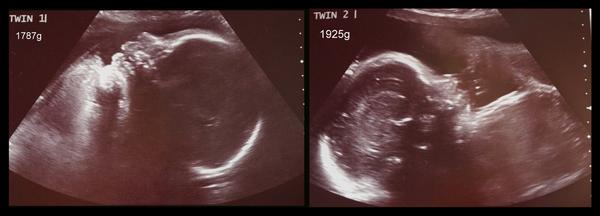

@danfal ... uzasnaci!!! 😉 Gratuluji, je to nadhera 😵 . Kolik deti vazily?

@atita24 hele záleží na tobě. ptala jsem se co je lepší, tak mi zdrav. sestra řekla že lepší je epidural, tak jsem jí řekla že se toho bojím (dělají mi zle nemocnice).....tak mi řekla, že teda jestli se bojím tak lepší narkóza 🙂 já bych to fakt nedala účastnit se vlastní operace....ale každý je jiný a nemocnice zvládá líp. Já šla raději na jistotu.....holky měly 2,17 kg a 2,3 kg (odhad před porodem byl teda 2,5 kg) ale váhy byly krásný na dvojčátka, ale stejně musely být pod dohledem.....za 12 dní jsme jely domů 🤐

@atita24 Ahoj, jak tak koukám jsme na tom dost podobně. Čekám jednovaječná dvojčátka-chlapečky, ale jeden je špatně vyživován placentou a tak budou muset jít ven dřív. Pan doktor nám dává tak ještě 3 týdny což by odpovídalo 32. týdnu. Císaře se nebojím, ale numím si představit tak malá miminka váhový odhad máme A-1430g a B-990g. Jak jste na tom vy?